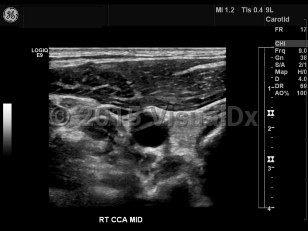

Carotid artery dissection

Carotid artery dissection is tearing of the carotid artery wall between the intimal and medial layers, resulting in an abnormal collection of blood or intramural hematoma. May compromise the arterial blood flow, causing ischemic stroke. Painful condition. Characteristic findings include headache and/or neck pain on the side of the dissection, periorbital headache / pain, miosis, ptosis, amaurosis fugax, tinnitus, facial numbness, dysgeusia, tongue paresis, and syncope. Caused by a weakness in the arterial wall. Sometimes the result of blunt trauma to the neck or head as a result of a sports injury, strenuous exercise, whiplash, childbirth, or sexual intercourse. Certain conditions may compromise the strength of the arterial wall, including Marfan syndrome, fibromuscular dysplasia, atherosclerosis, Ehlers-Danlos syndrome type 4, and homocystinuria.